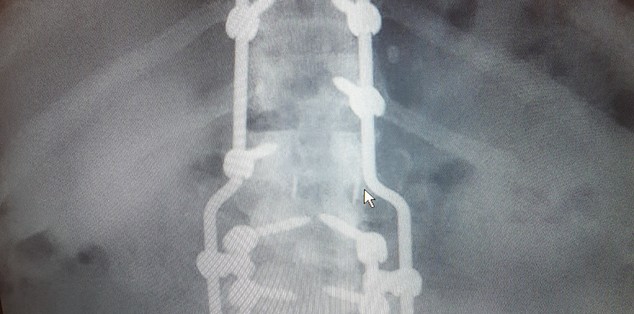

Michael - Lumbar Fusion

I has degenerative disc disease, severe leg pain,numb feet and numb toes. I had all five Lumbar Disc's fused, by Doctor Alexander Vaccaro. That procedure eliminated the leg pain, the numbness is gone, and the nerve pain is gone. I can not say enough hings about Dr. Vaccaro, he is in a class above Excellent, that few Doctors reach. You can not get better care, anywhere in the country, than at Rothman.